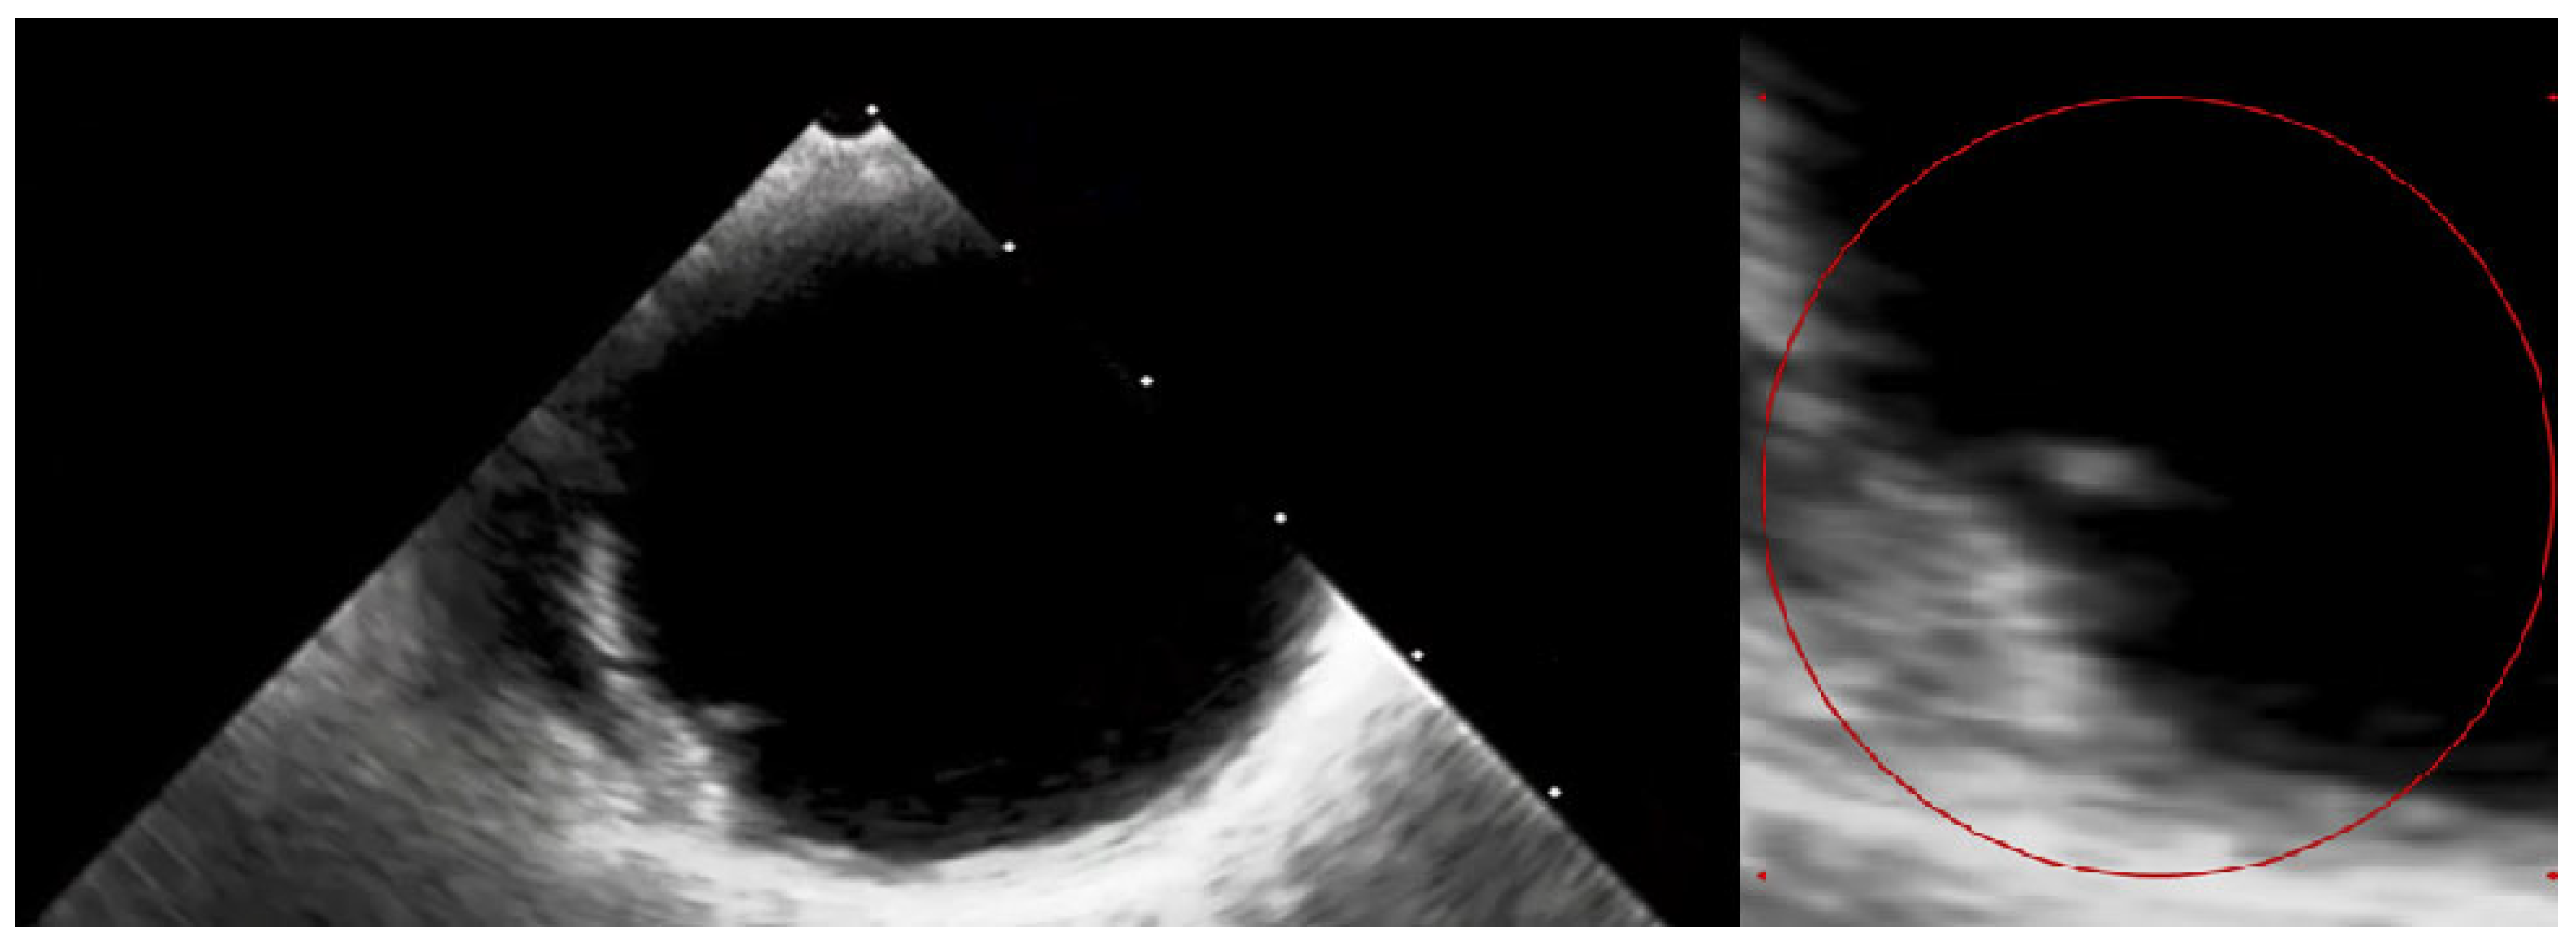

Figure 4. The transthoracic echocardiography showed a reduction in the gradients through the aortic valve prosthesis with parameters similar to that after the TAVI (on left: post-TAVI; on right: post-LMWH treatment). According to the 2021 ESC/EACTS Guidelines, in patients after TAVI, lifelong SAPT is recommended in the lack of indications for oral anticoagulants (OACs) [1]. However, despite similar recommendations for aspirin, the 2020 ACC/AHA Guidelines suggest that in patients with a low bleeding risk, it is worth acknowledging the antithrombotic prophylaxis with DAPT or VKA [2]. The direct-acting oral anticoagulants (DOACs) were not found to be superior to the administering antiplatelet or VKA, and in patients without indications for OAC, were linked to a higher incidence of all-cause mortality [3,4,5]. The 2021 ESC/EACTS and 2020 ACC/AHA Guidelines for managing valvular heart disease indicate that anticoagulation using VKAs or UFH is a first-line therapy for bioprosthetic valve thrombosis. Such an approach is highly effective in the normalization of valve function in 85% of the patients [6].